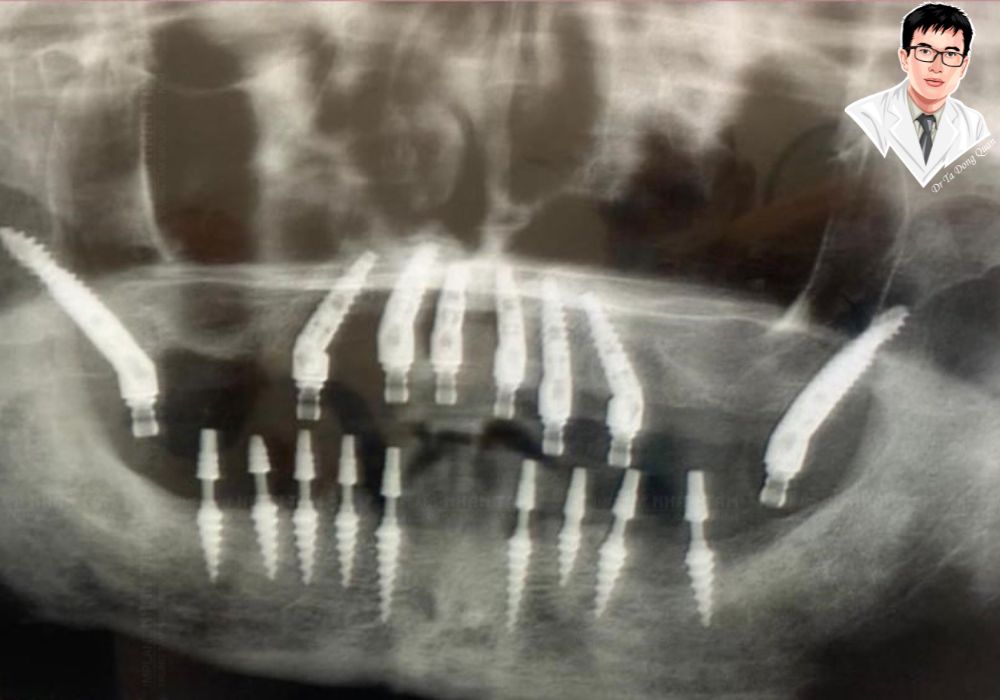

3. Nhận diện và đánh giá trụ implant nha khoa cao cấp

Những thương hiệu cao cấp như Straumann (Thụy Sĩ), Nobel Biocare (Mỹ) hay Megagen (Hàn Quốc) không chỉ nổi bật bởi chất liệu mà còn ở độ chính xác của ren xoắn, khả năng phân bổ lực nhai và độ an toàn sinh học. Các loại trụ này thường được bác sĩ chỉ định trong những trường hợp cần phục hình toàn hàm hoặc xương hàm yếu, giúp đảm bảo độ ổn định tối đa và hạn chế biến chứng.

3. Nên chọn trụ implant nào phù hợp với xương hàm và tình trạng mất răng

Người có xương hàm khỏe, mật độ xương tốt có thể chọn implant tầm trung như Dentium hoặc Megagen để tối ưu chi phí trồng răng. Với những trường hợp tiêu xương hoặc mất răng lâu năm, bác sĩ thường khuyên dùng trụ cao cấp Straumann, có khả năng tích hợp nhanh và độ ổn định cao, giảm nguy cơ thất bại sau cấy ghép.